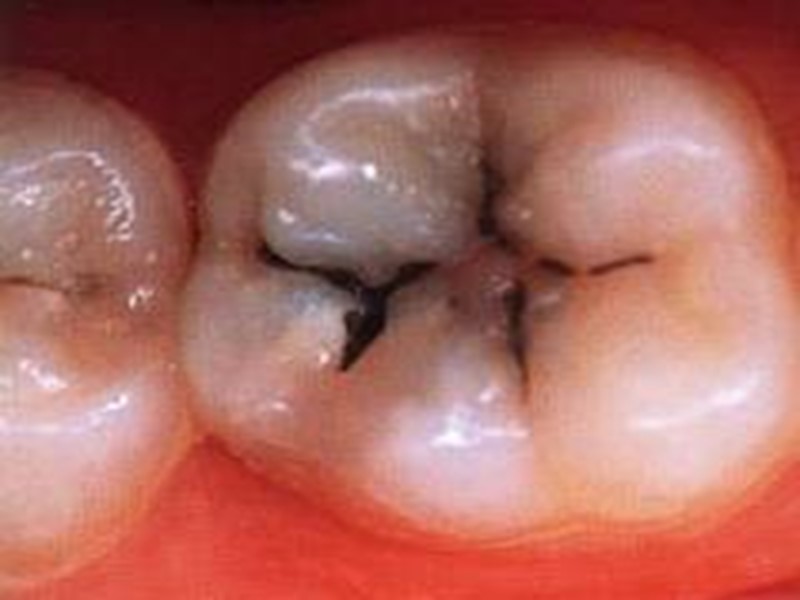

Классификация по локализации: Фиссурный кариес. Контактный (апроксимальный) кариес. Пришеечный (цервикальный) кариес. Циркулярный (кольцевой) кариес.

Первый класс

Классификация кариозных полостей по Блеку 1 класс – полости, расположенные в области фиссур и естественных углублений (например, слепая ямка верхних латеральных резцов); 2 класс – полости, расположенные на контактных поверхностях моляров и премоляров; 3 класс – полости, расположенные на контактных поверхностях резцов и клыков при сохранении режущего края; 4 класс – полости, расположенные на контактных поверхностях резцов и клыков с нарушением углов и режущего края коронки; 5 класс – полости на губных, щёчных и язычных поверхностях, расположенных в придесневой части коронки. В последнее время выделяют 6 класс, который не описал Блек, это полости, расположенные на буграх моляров и премоляров и на режущем крае резцов и клыков